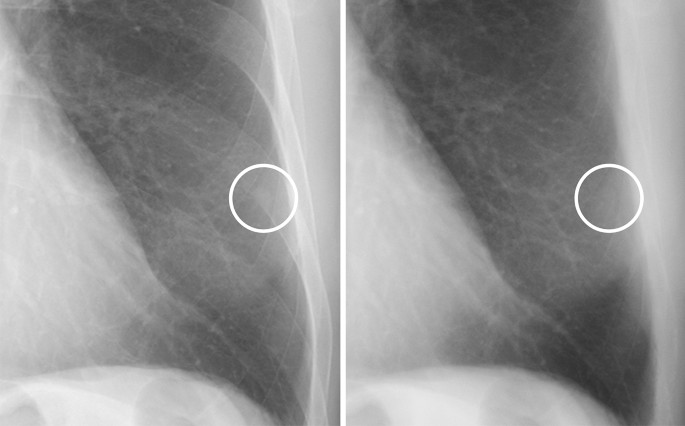

Representative images of nodules that were correctly diagnosed using soft tissue images are shown in Figs. 1, 2, 3 and 4.

A case of a calcified nodule overlapping with the bone. (left) On the standard image, the evaluation of the presence or absence of calcification among readers was not consistent (confidence level of each reader: 4, 3, 3, 4 and 2, respectively). (right) In the soft tissue image, the nodule disappeared. All readers correctly evaluated it as calcified (confidence level of each reader: 1, 1, 2, 2 and 2, respectively).